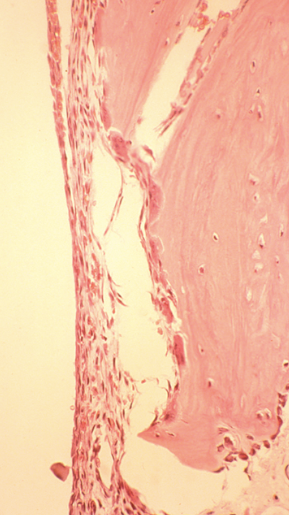

What is seen on histology of unicameral bone cysts?

What is the histology of aneurysmal bone cyst?